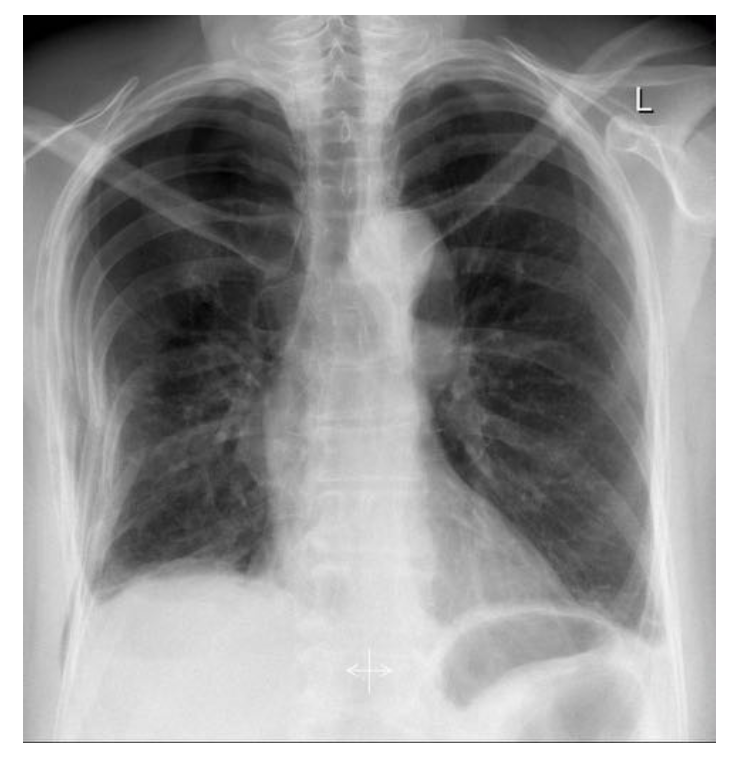

18

Q

Where is the pathology?

A

• Multiple right-sided rib fractures.

• Pneumothorax.